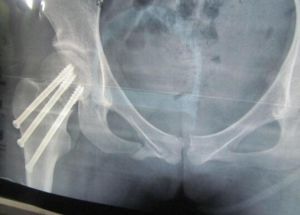

血腫內麻醉或臂叢神經阻滯下行閉合復位與柯萊斯骨折整復相反,術者將傷腕伸直位牽引助手於肘部作反牽引,在牽引的同時術者由掌側向背側推擠遠折端使骨折復位,此種骨折整復較易,但維持整復位置較困難整復後,用短臂前後石膏托固定腕於輕度背伸位前臂與鏇轉中立位2周,再改為腕關節中立位固定2周對骨折位置極不穩定或復後,再次移位的骨折。可考慮行切開復位甩小型“T”字鋼板螺絲釘作內固定或用托狀鋼板(buttressplate)作內固定。